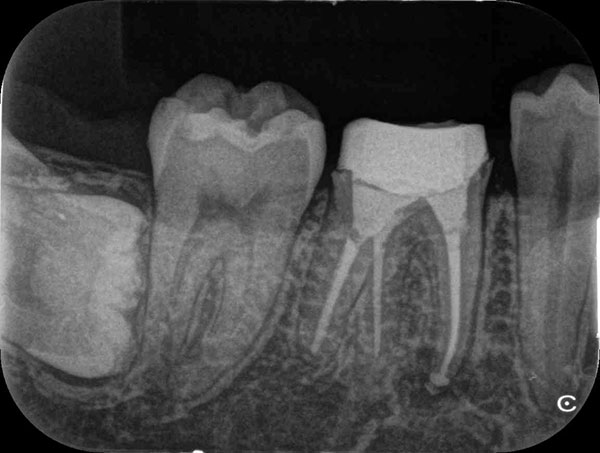

術前

術後

症例について

主訴:

硬いものを食べると違和感があり疲れたら歯が浮いてる様な感じがする

治療内容:

過去に行った根管治療をやり直し、再感染の原因を取り除く治療です。

治療期間:各90分 2回

費用:クラウンコア除去 5,500円(税込)/ 隔壁形成 5,500円(税込)/ 再根管治療 132,000円(税込)/ 築造 16,500円(税込)

治療に関わるリスクまたは副作用:

症状が改善しない場合、外科的歯内療法または抜歯が必要になることがあります。